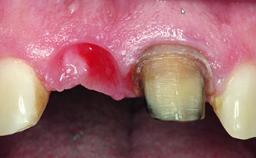

Loading Protocol Immediate

Provisional Implant-Supported Prosthesis Prosthodontic margin < 3 mm apical to mucosal margin Prosthodontic margin < 3 mm apical to mucosal margin

A healthy 23-year-old female patient was referred for a consultation on replacing tooth 21 with an implant-supported restoration. The patient had recently moved to the area and reported a history of endodontic and periodontal treatment for tooth 21. The tooth had been deemed non-restorable by her previous periodontist but since she was going to be moving, he recommended consulting to a dentist in her new city to continue her treatment. A review of her medical history yielded no significant findings and no known drug allergies. The analysis of her smile revealed a medium to high symmetrical smile line and a slightly discolored tooth 21.